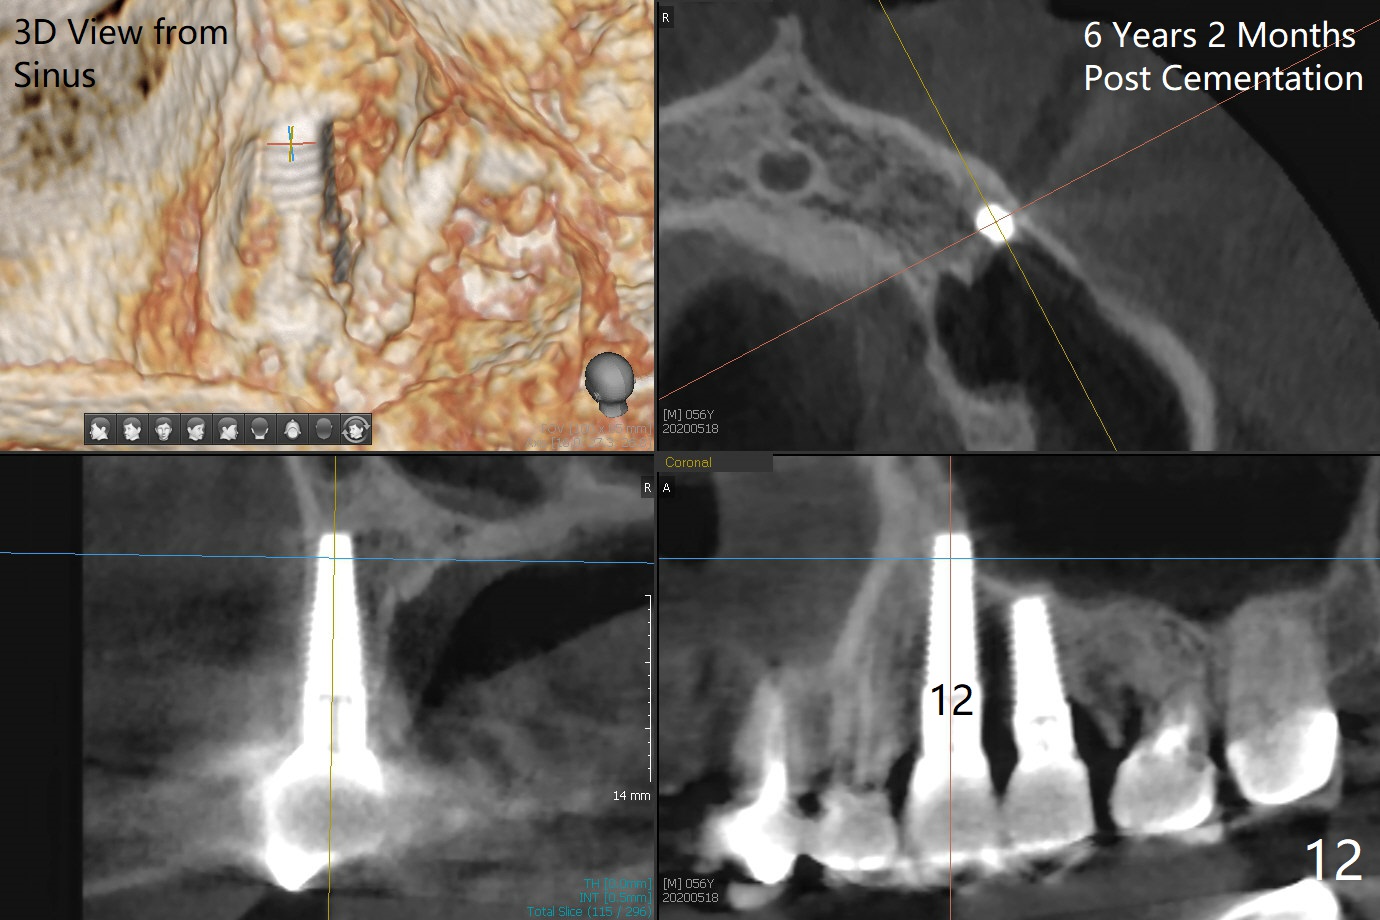

A 50-year-old man has mild pain in the upper left 1st bicuspid 3 years after root canal retreatment with placement of two posts (Fig.1). Findings of clinical exam are consistent with root fracture (Fig.2). Extraction reveals two fused roots (Fig.3,4). Probing indicates that the buccal plate is defective. Osteotomy is initiated in the palatal socket with a 2 mm pilot drill, followed by 2.5 and 3.0 mm reamers and 4.5x20 mm tap. The septum appears to have been pushed buccally (Fig.5 *) and form a new buccal wall (partially, strengthened by bone graft mentioned below) for the implant to be placed. The implant (4.5x20 mm) is placed in the palatal socket (Fig.6 *) with insertion of an abutment (A: 3.5x5 mm 0º), while a mixture of autogenous bone (harvested from reamers) and Synthograft (Bicon) is placed in the shrunken buccal socket (Fig.7; using allograft may decrease postop bony shrinkage). The bone graft is then contained by an immediate provisonal without collagen membrane or flaps. The patient is doing well postop. The gingiva is healthy (Fig.8*) when the provisional is removed 3 months postop with normal papillae (Fig.9 arrowheads). It remains the same 1 month post cementation (Fig.10,11). For further follow up, see immediate implant of the tooth #13.